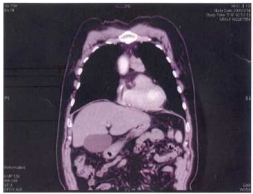

74.一位30歲女性至急診就醫,主訴突發性胸痛,長期呼吸困難,胸部電腦斷層影像如附圖,下列 敘述何者錯誤?

(A)影像表現與 tuberous sclerosis在肺部的病灶相似度高 (B)此病人可能發生自發性氣胸 (C)男性的發生率與女性相當 (D)除了肺部之外,也可能會在腎臟、神經系統等部位出現異常